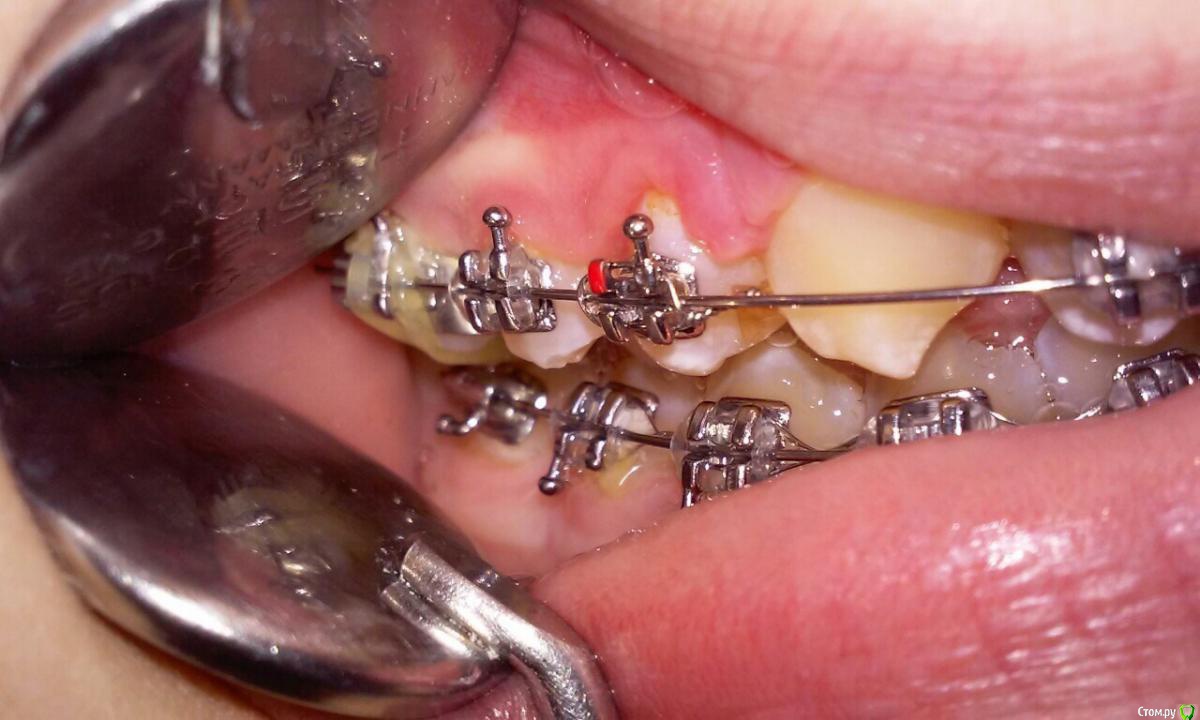

natkoorth1991 Опубликовано 24 октября, 2015 Автор Поделиться Опубликовано 24 октября, 2015 дык это чистая биомеханика, я не понял изначально в чем вопрос)) Одностороннее применение Эластика 6 унций 3/16 приводит к смещению в сторону тяги, с противоположной стороны все в прикусе. вопрос: нужно ли на той стороне, где все ок применять эластик для " равновесия", чтоб челюсть не смещалась?)) Ссылка на комментарий

natkoorth1991 Опубликовано 24 октября, 2015 Автор Поделиться Опубликовано 24 октября, 2015 Клык еще не допрорезался, 16 круглая дуга на в/ч Ссылка на комментарий

natkoorth1991 Опубликовано 25 октября, 2015 Автор Поделиться Опубликовано 25 октября, 2015 а зачем вы работаете на круглых дугах ?почему не на па зачем вы работаете на круглых дугах ?почему не на прямоуголных?. На в/ч этап нивелирования, пока клык в систему не включу. эластик будет на прямоугольных, к проблеме готовлюсь заранее. пациентку предупредила о возможности последующего применения эластиков. По просьбе пациентки попробовали одеть эластик, такая возможность была , так как уже имеется кнопка на нижнем моляре с язычной стороны, она пожаловалась на перекос челюсти , вот и возник вопрос. Ссылка на комментарий

Ayrat_zub Опубликовано 31 октября, 2015 Поделиться Опубликовано 31 октября, 2015 Одностороннее применение Эластика 6 унций 3/16 приводит к смещению в сторону тяги, с противоположной стороны все в прикусе. вопрос: нужно ли на той стороне, где все ок применять эластик для " равновесия", чтоб челюсть не смещалась?))а вы смотрели нет ли изначального смещения нижней челюсти? в иедале для начала вам нужно укрепить позицию верхних моляров, бюгелем, или хотябы полноразмерной дугой, в остальном не вижу причины использовать эластик с противоложной стороны Ссылка на комментарий